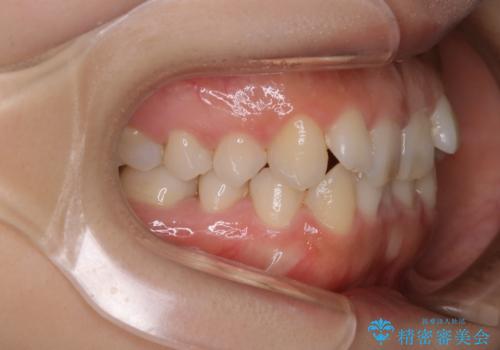

上顎の前歯の傾きを改善することで、がたつきを治すためのスペースを確保しました。

また、それだけではがたつきを改善するスペースが不足していたため、歯の側面を削りがたつきを改善しました。

下顎については、歯の側面を削ることをメインにがたつきを改善しました。

今回、奥歯のかみ合わせに問題がなく、前歯のがたつきのみの対応だったため、インビザライン モデレートというものを使用しました。インビザライン モデレートは歯を動かせる枚数が、最大26枚までと制限があります。お口の中の状態をよく精査し、どの種類のインビザラインを使用するかを判断しています。